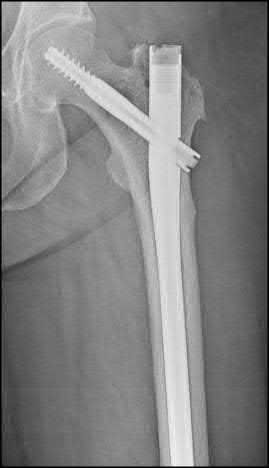

Question 1:

A 12-year-old obese boy presents with vague left thigh and knee pain. He is diagnosed with a Slipped Capital Femoral Epiphysis (SCFE) as seen in similar clinical scenarios. During percutaneous in-situ fixation, unrecognized penetration of the guide wire into the hip joint occurs. What is the most likely specific complication resulting from this technical error?

Correct Answer: Chondrolysis

Explanation:

Chondrolysis is a severe complication of SCFE characterized by rapid destruction of the articular cartilage. While it can occur idiopathically, its most established iatrogenic cause is unrecognized intra-articular hardware penetration. The 'approach-withdraw' fluoroscopic technique is required during pinning to assure pins are entirely intraosseous. Avascular necrosis (AVN) is usually due to damage to the epiphyseal blood supply (retinacular vessels) secondary to the initial displacement, forceful closed reduction, or posterosuperior pin placement.